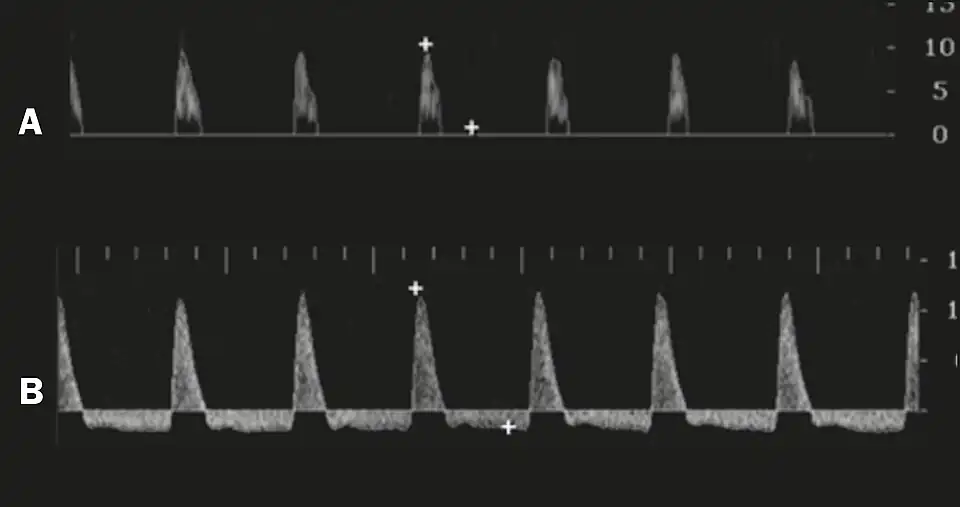

Before the injection of the chosen drug, the flow pattern is monophasic, with low systolic velocities and an absence of diastolic flow. After injection, systolic and diastolic peak velocities should increase, decreasing progressively with vein occlusion and becoming negative when the penis becomes rigid (see image below). The reference values vary across studies, ranging from > 25 cm/s to > 35 cm/s. Values above 35 cm/s indicate the absence of arterial disease, values below 25 cm/s indicate arterial insufficiency, and values of 25–35 cm/s are indeterminate because they are less specific (see image below). The data obtained should be correlated with the degree of erection observed. If the peak systolic velocities are normal, the final diastolic velocities should be evaluated, those above 5 cm/s being associated with venogenic ED.[48]